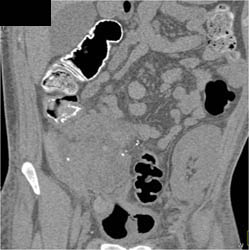

Pancreatic Necrosis With Splenic Vein Occlusion